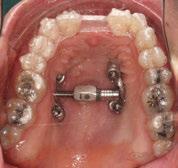

3. Fase quirúrgica final

A los 6 meses de cicatrización, se realizó un nuevo CBCT, obteniendo un nuevo archivo DICOM que alineamos con el STL del encerado. De esta manera, se planificó la posición de los implantes a 4 mm del margen de la restauración final y se diseñó y confeccionó la férula de cirugía guiada dentosoportada en 12-13 y 22-23, la cual imprimimos con la impresora 3D Formlabs®. El provisional

de carga inmediata lo diseñamos con el programa de diseño 3D Exocad® a partir del encerado y se imprimió también en clínica con la misma impresora 3D (Figuras 14-16).

La cirugía se realizó bajo sedación consciente y anestesia local (articaína 4% con epinefrina 40/0,01 mg/ml Ultracain®, 5 carpules en vestibular y palatino de la arcada superior). En primer lugar, se realizaron las exodoncias de los dientes remanentes 11, 21 y 24 y, a continuación, se adaptó la férula de cirugía guiada dentosoportada, insertando los implantes elegidos, en este caso en las posiciones 11 y 21 de Zimvie Tapered Screw-Vent Z3D de 3,7 por 13 mm, 14 Zimvie Tapered Screw-Vent Z3D de 3,7 por 13 mm y 16, 24 y 26 de Zimvie Tapered Screw-Vent Z3D de 4,7 por 13 mm, quedando todos ellos a un torque mayor a 30 Nm. Posteriormente, se realizaron el resto de exodoncias,

Seguidamente, se colocaron los pilares cónicos TSV-TM de Zimmer® y se atornillaron los pilares provisionales de titanio (Figuras 17-23).